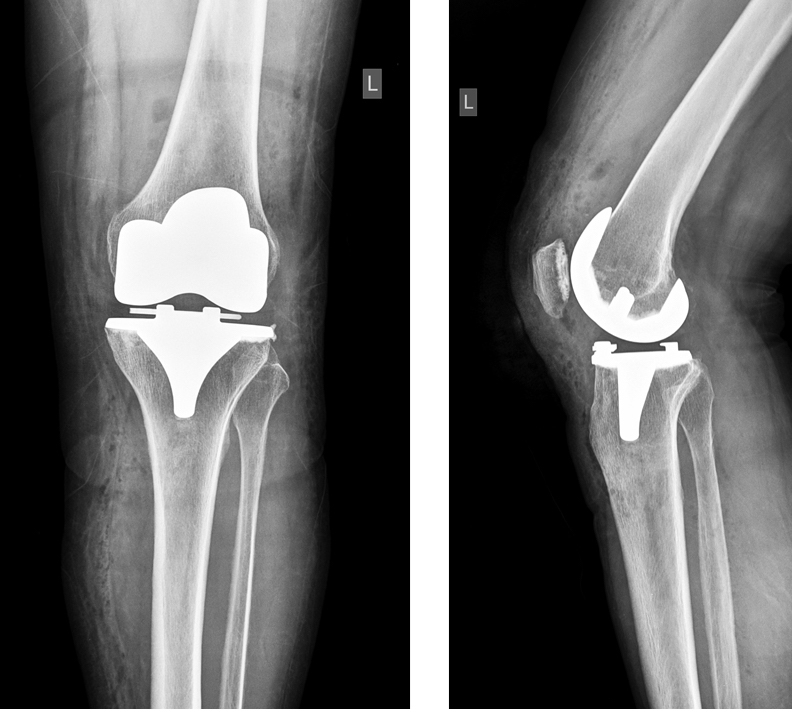

Течение раннего послеоперационного периода было неосложненным, пациентка в удовлетворительном состоянии выписана на 4-е сут. послеоперационного периода с амплитудой движений в коленном суставе 0°/0°/95° (разгибание/0°/сгибание). На амбулаторном этапе пациентка в домашних условиях продолжила реабилитацию, включавшую ходьбу с дополнительной опорой на костыли и комплекс упражнений лечебной физкультуры. С ее слов, вне связи с травмой незначительный болевой синдром, беспокоивший после операции, в течение нескольких дней стал крайне выраженным, был локализован в переднемедиальном отделе коленного сустава, стала ограниченной амплитуда движений. Больная обратилась к лечащему врачу. Было рекомендовано выполнение рентгенограмм коленного сустава в двух проекциях: диагностирована миграция фиксирующего вкладыш элемента (рис. 3).

Рис. 3. Рентгенограммы коленного сустава с признаками миграции фиксирующего элемента вкладыша

Fig. 3. Knee X-rays with signs of migration of the insert locking element